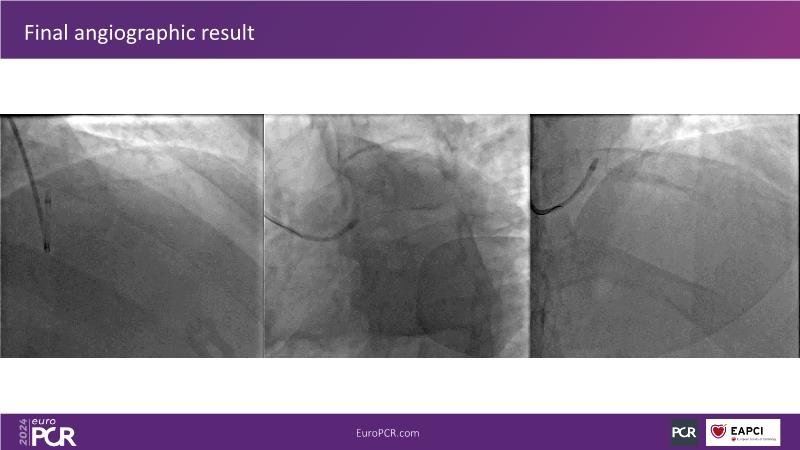

Explore this session to uncover the common association between calcium and acute coronary syndrome, and how intravascular lithotripsy (IVL) offers a safe solution for calcified lesions, with comparable procedural success rates. However, note that ACS cases involving calcium may lead to higher major adverse cardiac events (MACE). Special attention is warranted for women due to their propensity for adverse outcomes. Discover how the C2 + IVL catheter enhances procedural flexibility, yet high intracoronary imaging rates did not yield differences in MACE. Additionally, learn about the potential role of IVL in treating in-stent restenosis (ISR).

- To understand the best strategies to safely deal with calcium in ACS patients

- To share clinical experience to uncover practical tips and techniques for intravascular lithotripsy in complex calcified lesions